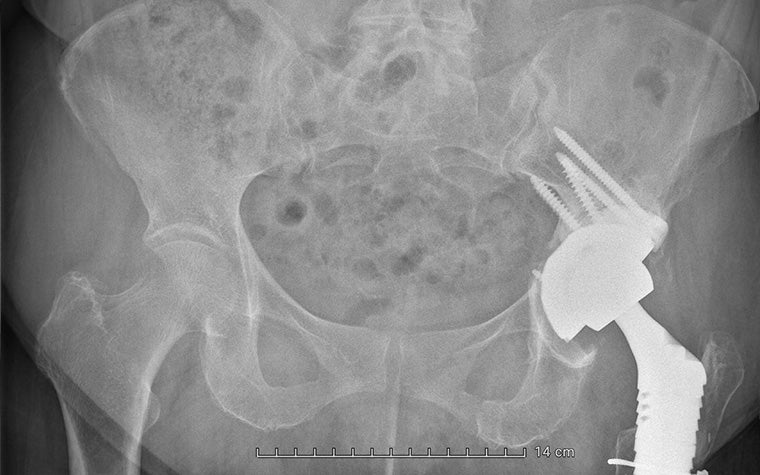

A few years ago, she suffered a periprosthetic fracture of the femur caused by polyethylene wear. Dr. Van Overschelde performed revision surgery with a REEF prosthesis on the femoral side and an acetabular revision with a revision cup and augment.

Then, six months ago, the patient began experiencing ongoing groin pain and difficulty walking after a fall. A CT scan revealed another periprosthetic acetabular fracture with a complete dissociation of the pelvis. The fracture was severe enough that natural healing was, unfortunately, not occurring.

Beyond these complications, the patient also had severe osteoporosis and a history of pseudo-tumor development, resulting in significant bone destruction. It was no straightforward case for Dr. Van Overschelde, and he had to navigate many complexities to restore function and minimize the risk of future medical interventions.

The aMace implant helps surgeons break the revision cycle. It is designed for minimal risk of dislocation, is based on unique 3D pelvis analyses to quantify bone loss and available bone stock, and makes long-term fixation possible with crossed screw trajectories and a defect-filling porous augment.

This comprehensive preparation was a major contributor to Dr. Van Overschelde executing the surgery successfully. He immediately felt very confident in the result: “I expected the reconstruction to be very stable, allowing the patient to fully bear weight and regain mobility immediately."

“At 7 am the day after the surgery, the patient was already standing and washing up at the sink. It’s a remarkable testament to the immediate impact of the implant and the procedure.”